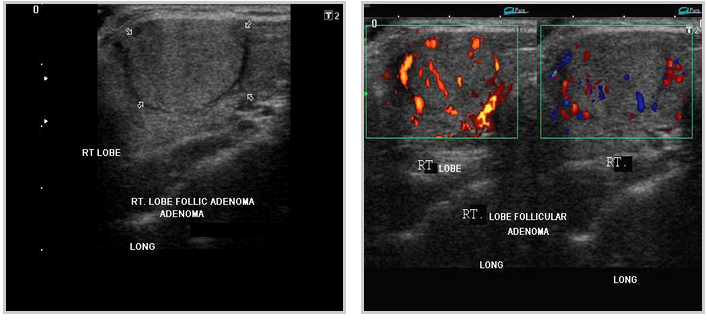

Pics form ultrasound-images.com :

ADENOMAS

thyroid_adenomatous nodules thyroid_follicular adenoma

FOLLICULAR ADENOMAthyroid_follicular adenomas